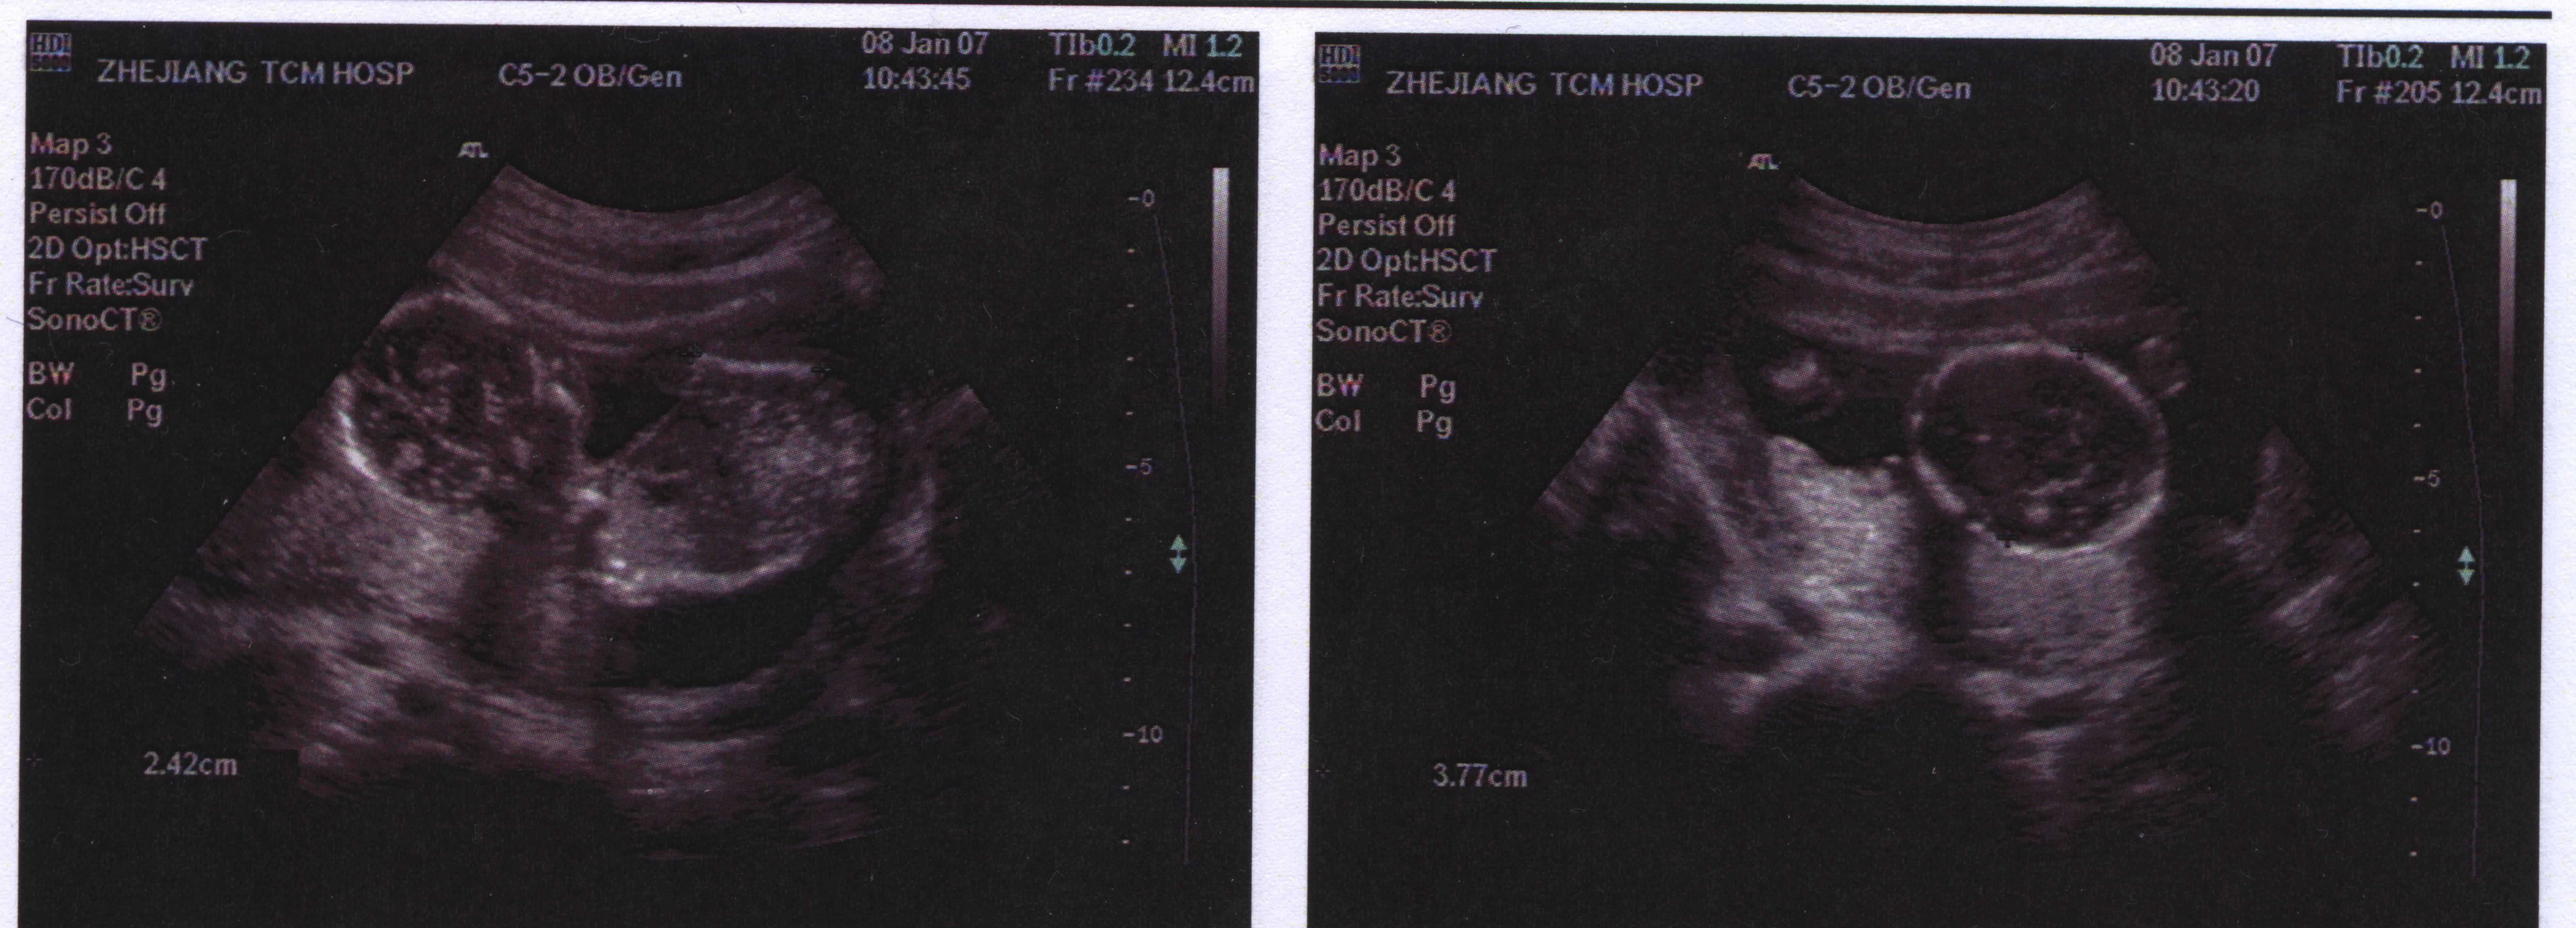

This is the second picture of our baby, this is 4 weeks after the first one. he/she is realy starting to look like a baby now. As you can see, the facial features are visable, so is the spine and if you look close enough, you can also see the heart. This is the time,I know I will be a father and I can't wait till the baby is born.

We still don't know if it's a boy or girl, this is not a big concern, we just hope the baby is healthy.